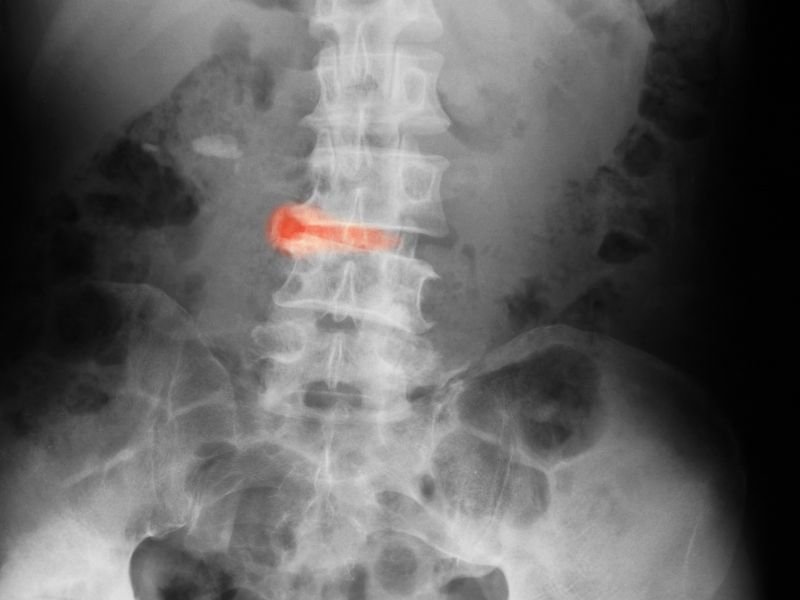

Intervenções cirúrgicas

Embora muitos casos de desordens articulares possam ser tratados com medicações e terapias físicas, em alguns casos, a cirurgia é necessária para aliviar os sintomas ou corrigir danos estruturais nas articulações. As intervenções cirúrgicas podem variar de procedimentos minimamente invasivos a cirurgias mais complexas.